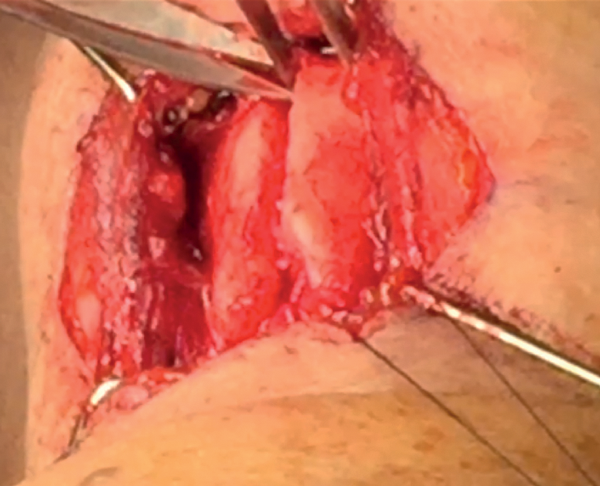

Completion of inner perichondrial elevation

The third stage is performed after drilling and separating the cartilage in the midline.

The inner perichondrium is freed by sharp scissor dissection laterally and towards the centre by just 2mm (Figure 13). This step is performed to allow ease of sliding in the bridge superiorly and inferiorly.

Figure 13: Completion of inner perichondrial elevation.